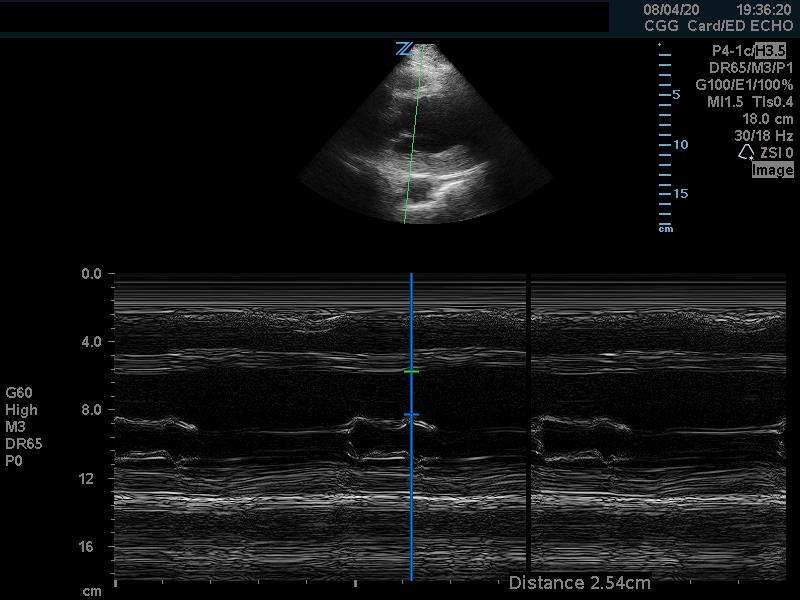

Fractional shortening can be used to estimate EF. This is performed by placing an M-mode spike through the anterior and posterior walls of the LV at the mid-LV in the parasternal short axis view. In M-mode, the diameter of the left ventricular cavity is measured in end-diastole (LVEDD) and end-systole (LVESD). One can then apply the below formula to obtain an estimation of EF%:

FS = (LVEDD-LVESD/LVEDD) x 100%

A normal EF is suggested by a percent FS between 25-45%. (Fig. 7,8)13

Figure 7. Fractional shortening measurement obtained using M-mode, indicating LV systolic function within normal range